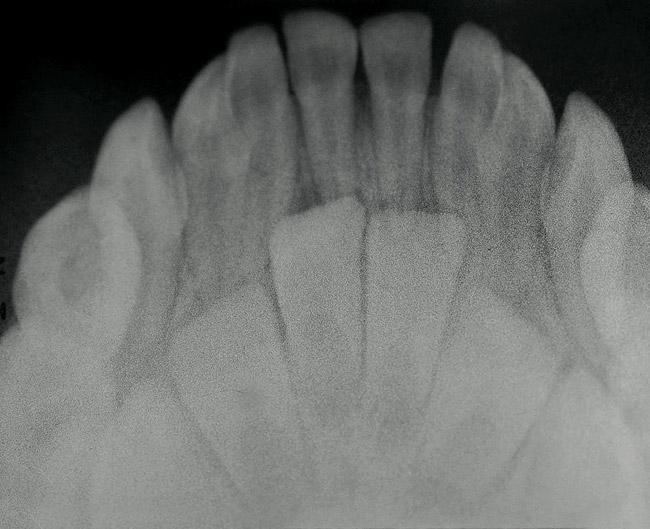

Twinning Teeth

Double Dental Twinning in Two Children | May 2012 | Inside Dentistry Twinned Tooth - Stock Image - C039/3027 - Science Photo Library Double Dental Twinning in Two Children | May 2012 | Inside Dentistry Twinned Tooth - Stock Image - C039/3026 - Science Photo Library | Twinning Teeth

![Twinning Teeth 764x580 PDF] Mirror imaging of impacted and supernumerary teeth in ...](https://d3i71xaburhd42.cloudfront.net/afa4216936752db6fda0c3e724a25236cabda8b4/2-Figure1-1.png)